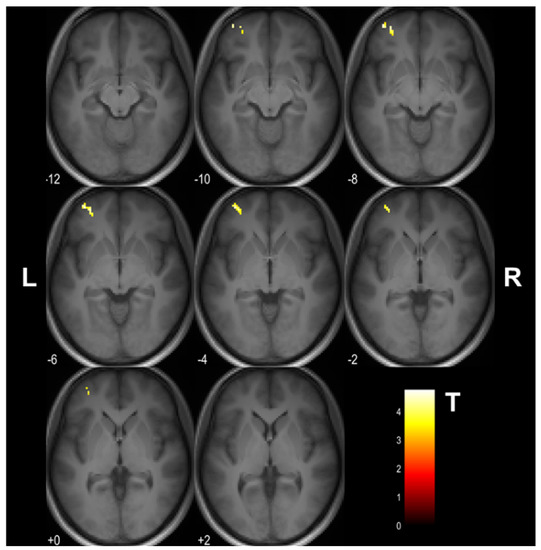

The training and time-related changes in μFA (F(1,27) = 13.54, uncorrected p < 0.001) were observed on 2 × 2 mixed-design ANOVA. Post hoc analysis revealed that the training group had a μFA decrease in the left middle frontal gyrus (uncorrected p < 0.001; 53 voxels; MNI coordinates: X = −36, Y = 54, Z = −6) following the cognitive training (Figure 3). Forty-three of these voxels were located in the gray matter, and the rest white matter. The mean μFA value of this region and the corresponding mean FA and MD values are given in Figure 4. No voxel with significant μFA increase after the training was observed. There were also no significant time-related changes in μFA in the control group. Similarly, no significant time-related changes in FA, MD, and the gray and white matter volumes were observed in both groups.

Figure 3. The cluster in the left middle frontal gyrus (MNI coordinates: X = −36, Y = 54, Z = −6) showing a decrease in μFA upon the 4 week cognitive training (uncorrected p < 0.001). The cluster is shown as an overlay on a 3D magnetization−prepared rapid acquisition gradient−echo (MPRAGE) template. The look−up table denotes T values. L and R indicate left and right, respectively.